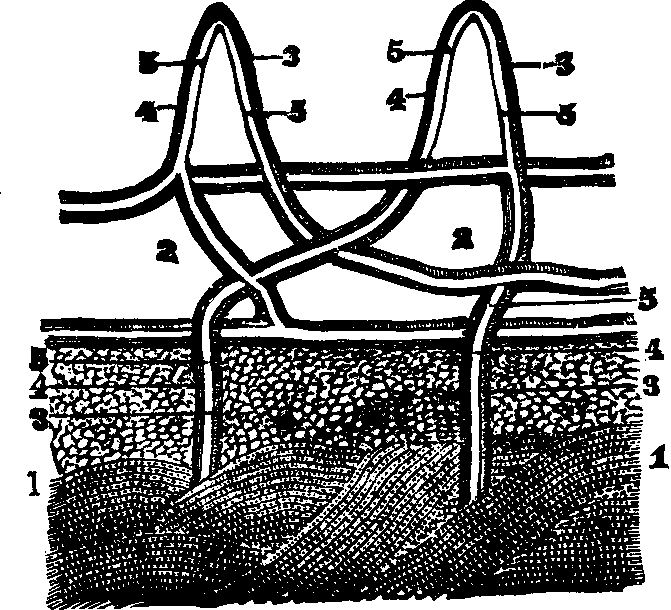

The Lymphatics are not less important organs in the process of absorption. Nearly every part of the body is permeated by a second series of capillaries, closely interlaced with the blood-vessels, collectively termed the Lymphatic System. Their origin is not known, but they appear to form a plexus in the tissues, from which their converging trunks arise. They are composed of minute tubes of delicate membrane, and from their net-work arrangement they successively unite and finally terminate in two main trunks, called the great lymphatic veins. The lymphatics, instead of commencing on the intestinal walls, as do the lacteals, are distributed through most of the vascular tissues as well as the skin. The lymphatic circulation is not unlike that of the blood; its circulatory apparatus is, however, more delicate, and its functions are not so well understood.

Fig. 37. 1. A

In all animals which possess a lacteal system there is also a lymphatic system, the one being the complement of the other. The fact that lymph and chyle are both conveyed into the general current of circulation, leads to the inference that the lymph, as well as the chyle, aids in the process of nutrition. The body is continually undergoing change, and vital action implies waste of tissues, as well as their growth. Those organs which are the instruments of motion, as the muscles, cannot be employed without wear and waste of their component parts. Renovated tissues must replace those which are worn out, and it is a part of the function of the absorbents to convey nutritive material into the general circulation. Researches in microscopical anatomy have shown that the skin contains multitudes of lymphatic vessels and that it is a powerful absorbent.

Absorption is one of the earliest and most essential functions of animal and vegetables tissues. The simpler plants consist of only a few cells, all of which are employed in absorption; but [pg 52]in the flowering plants this function is performed by the roots. It is accomplished on the same general principles in animals, yet it presents more modifications and a greater number of organs than in vegetables. While animals receive their food into a sac, or bag called the stomach, and are provided with absorbent vessels such as nowhere exist in vegetables, plants plunge their absorbent organs into the earth, whence they derive nourishing substances. In the lower order of animals, as in sponges, this function is performed by contiguous cells, in a manner almost as elementary as in plants. In none of the invertebrate animals is there any special absorbent system. Internal absorption is classified by some authors as follows: interstitial, recrementitial, and excrementitial; by others as accidental, venous, and cutaneous. The general cutaneous and mucous surfaces exhale, as well as absorb; thus the skin, by means of its sudoriferous glands, exhales moisture, and is at the same time as before stated, a powerful absorbent. The mucous surface of the lungs is continually throwing off carbonic acid and absorbing oxygen; and through their surface poisons are sometimes taken into the blood. The continual wear and waste to which living tissues are subject, makes necessary the provision of such a system of vessels for conveying away the worn-out materials and supplying the body with new.